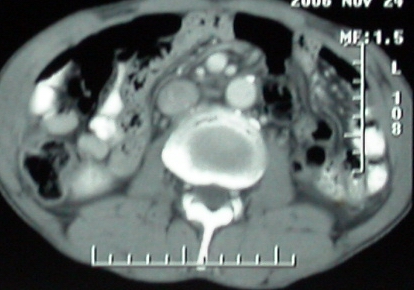

补充一点重要资料:今日查afp大于正常值10倍以上。因此,本病例最大可能应该是肝癌。

手术结果:

肝脏尾状叶肝癌(沿肝十二指肠韧带向下韧带内生长,门腔间隙外压增大),大结节性肝硬化,胆囊积脓,胆道感染。术中见肝外胆道2cm直径,肿瘤向前压迫胆管至扁平状态。